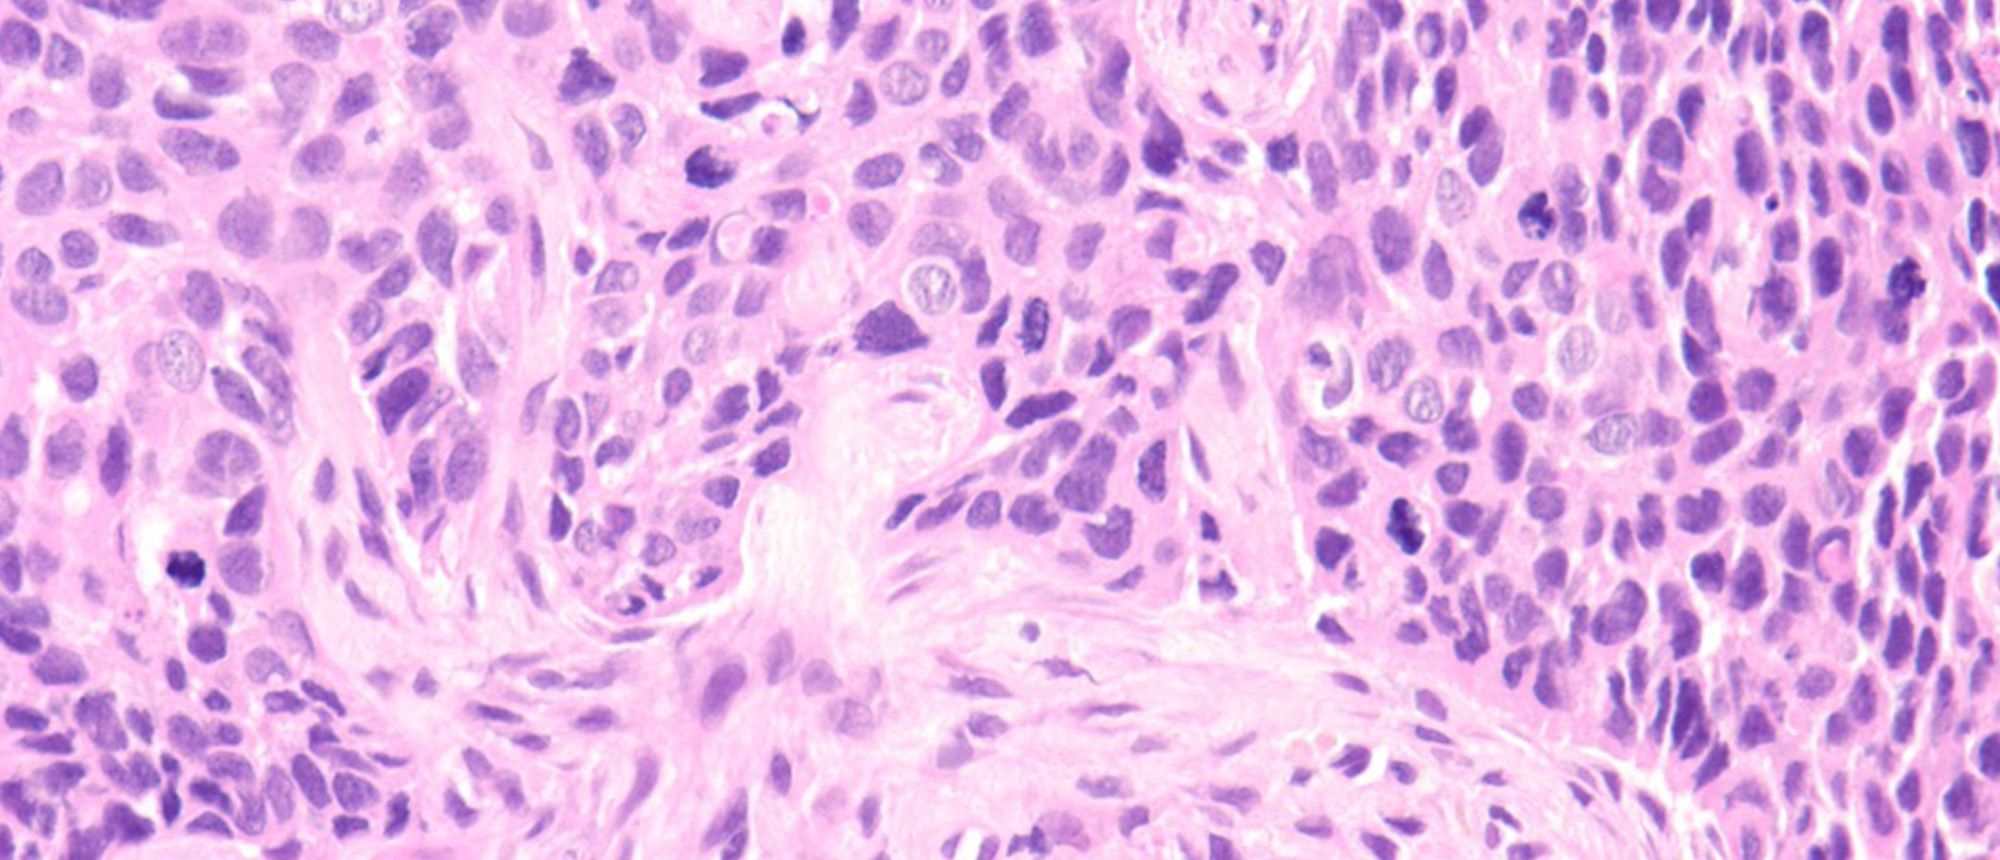

Squamous Cell Carcinoma of the Lacrimal Sac

Squamous Cell Carcinoma of the Lacrimal Sac A patient presented to the emergency department for a history of tearing on the right eye and medial canthal mass. He had a history of chronic sinus pain for months, initial examination was notable for increased tear lake on the right eye, along with an i…